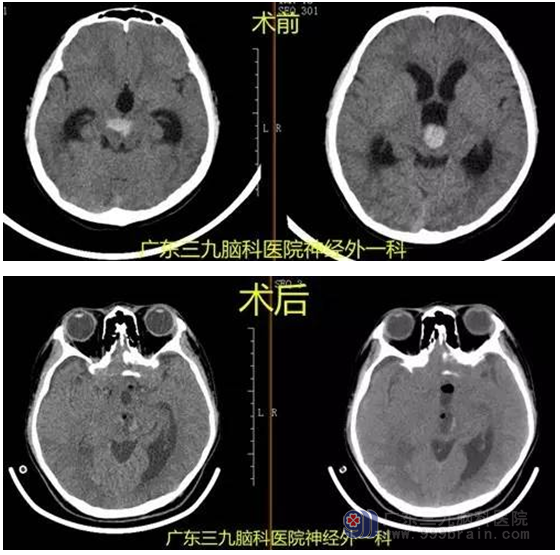

韦某某,男,14岁,头晕加重并伴视物重影入院。入院后完善相关术前检查,行全麻下中脑及大脑脚前池海绵状血管瘤切除术,手术由神经外一科主任张良主刀完成,手术过程顺利,术后患者恢复良好,未见并发症。术前影像报告提示中脑及大脑脚前池海绵状血管瘤,术后病理提示动静脉畸形,术后磁共振提示肿瘤全切。

脑动静脉畸形 (CAVM)是一种发病率高 ,病因未明的脑血管性疾病,主要表现为头痛、癫痫、出血等神经功能障碍,其危害性极大,是中青年致残或致死的主要因素。其平均发病年龄为31.2岁,男性稍多于女性。脑动静脉畸形的形成为脑血管发育异常所致,即在分化成动脉和静脉之前 ,原始毛细血管丛是一团毛细血管网。在血流和蜕变的共同作用下,原始血管丛有些血管腔融合,而有些血管腔溶解,最终分化出动脉和静脉,一旦在蜕变初期发育错误,就会形成脑血管畸形。中脑动静脉畸形是脑动静脉畸形中较为少见的一种类型,其发病率为脑动静脉畸形的2%-5%。本例患者为14岁男性,年龄较轻,入院时头颅CT显示高密度异常病灶,诊断为出血性脑血管疾病,病变范围约2.5cm*2.0cm,并造成梗阻性脑积水症状。

中脑动静脉畸形的治疗方法主要有手术切除、介入栓塞、放射治疗及以上方法相结合。但由于其位置较深,涉及到重要神经功能结构,单纯手术切除比较困难,风险较大。随着技术的进步,目前手术也能取得满意效果,手术时机我们倾向于出血后2周血肿吸收前手术为佳。本例患者从三脑室入路切除畸形,术后未见明确动眼神经损伤、瘫痪及意识障碍等并发症,术后恢复良好出院。